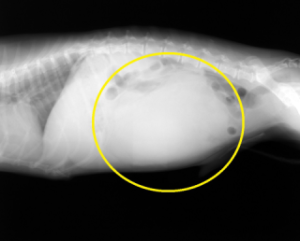

腹腔内腫瘍

術前のレントゲン写真

(黄色の丸の部分が腫瘍)

摘出した腫瘍